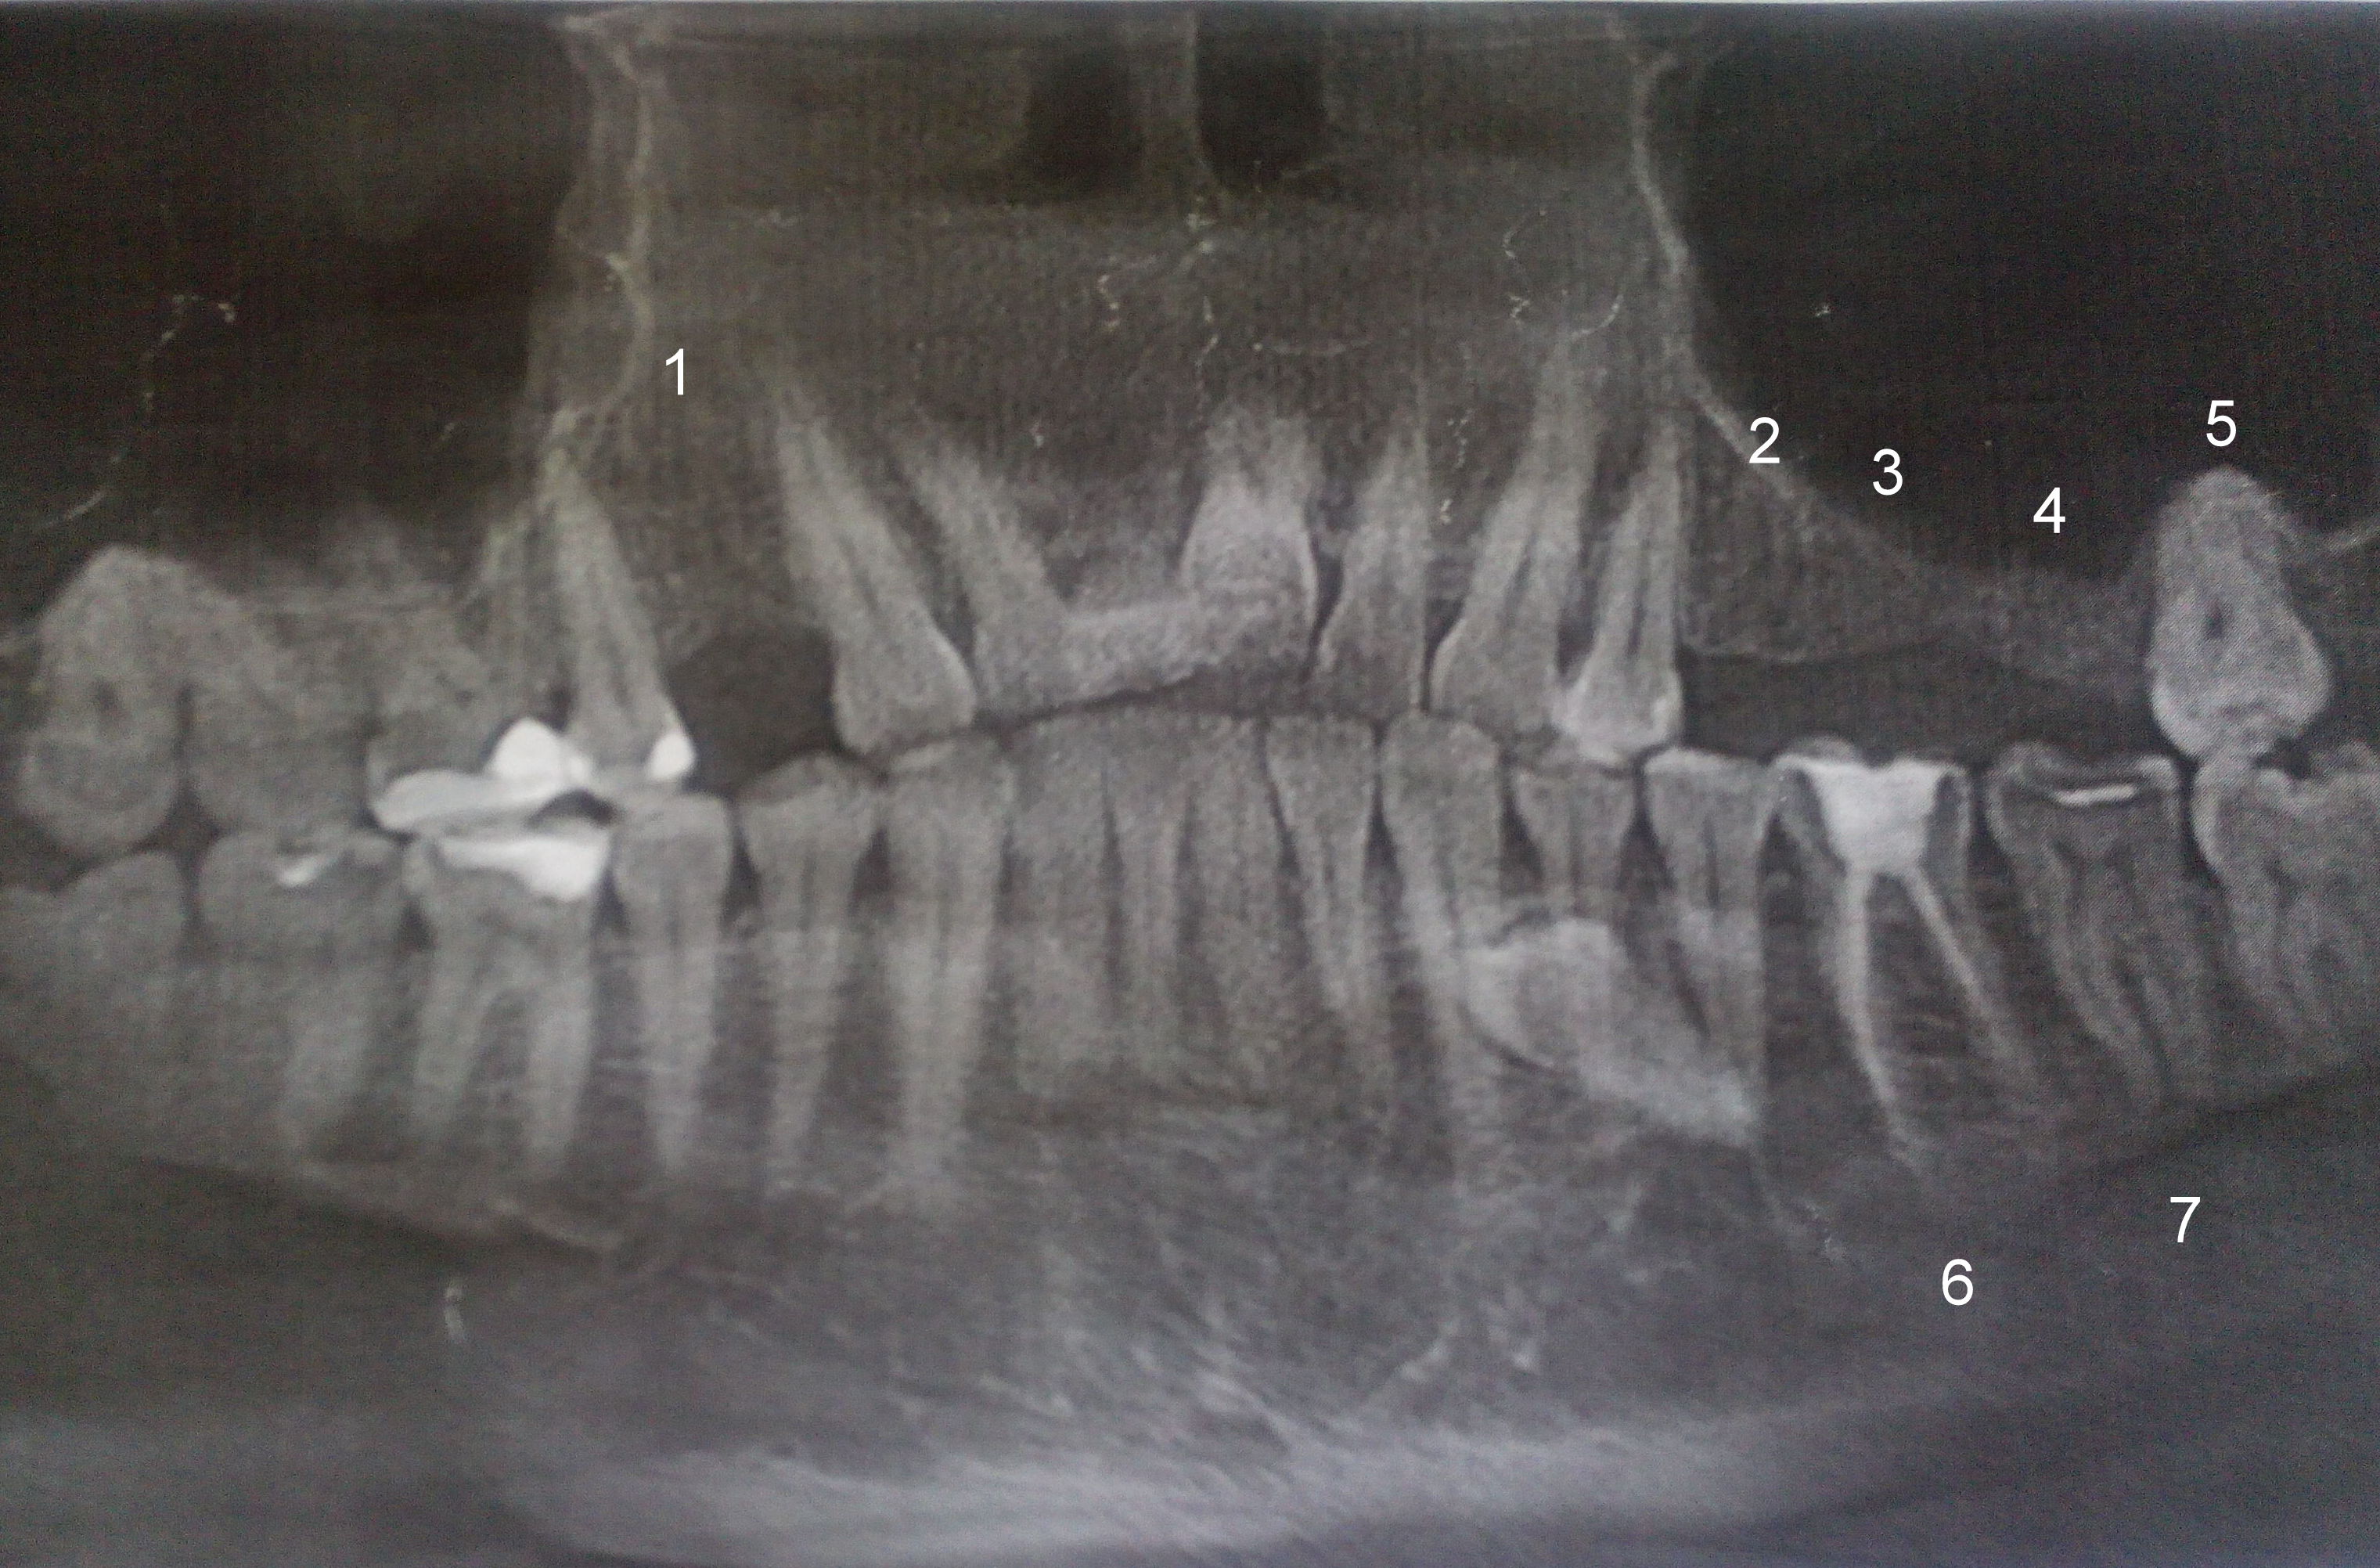

Прикрепленые фото

Начну с того, что у вас на нижней челюсти растет горизонтально зуб, что не может не сопровождаться если не болью, то обязательно дискомфортом и вы его могли испытывать на нижней челюсти.

Все остальное лично мне не понятно, судя по снимку, у вас ухоженная полость рта (была) и я считаю, что удалять зубы не стоило. Мне интересно посмотреть выписку врача невролога из стационара... По всем симптомам, судя по вашему рассказу, похоже на неврологию, но и на это должно быть причины и раздражители.